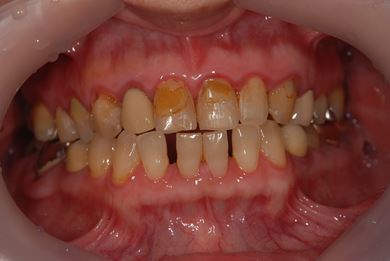

| 性別/年齢 | 女性 / 51歳 | ||||||||||||||||||||||||||||||||

| 主訴 | 前の歯の治療後の変色が気になる。詰め物がとれた箇所あり。痛みあり。 | ||||||||||||||||||||||||||||||||

| 治療方針 | セラミック治療にて、審美的回復を行う。 | ||||||||||||||||||||||||||||||||

| 治療内容 | オールセラミッククラウン7本(オールセラミック用土台1本)、ハイブリッドセラミッククラウン10本(ハイブリッドセラミック用土台9本)、ハイブリッドセラミックインレー1本 | ||||||||||||||||||||||||||||||||